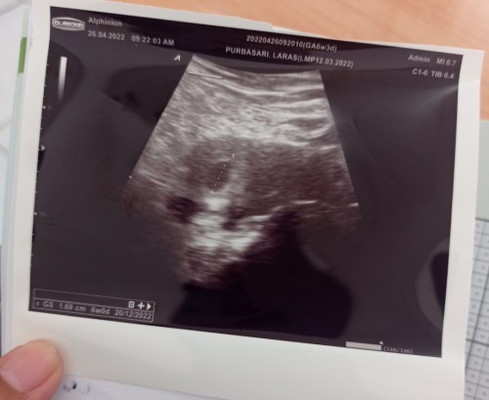

Hallo bunda, ini hasil USG waktu tgl 26 April 2022 baru terlihat kantung saja. Kata dokter nya habis lebaran di USG lagi biar ketahuan ada janin atau detak jantungnya. Sekarang Alhamdulillah sudah masuk usia 8week dan saya mau tanya bunda, Kira-kira saya USG kembali di usia kandungan berapa ya? Karena banyak yang bilang jangan keseringan USG apalagi kandungan masih kecil. 🥺 jadi membuat saya bingung harus balik ke dokternya lagi kapan. Terimakasih 🙏#seriusnanya #bantusharing #ingintahu